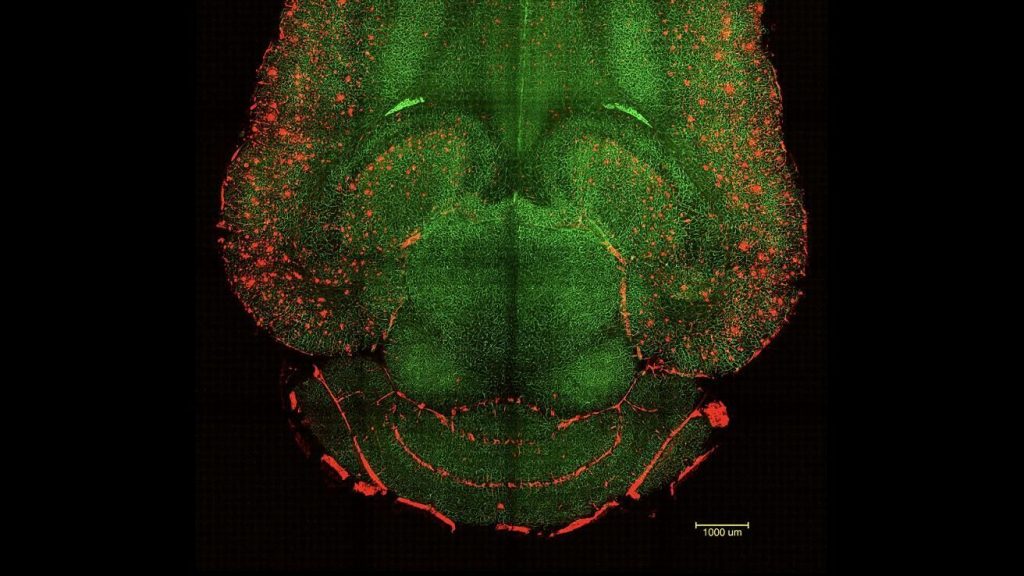

Imagen microscópica del cerebro de un ratón tratado con la nueva terapia basada en nanopartículas | IBEC

Un equipo científico co-liderado desde España por el Instituto de Bioingeniería de Cataluña (IBEC) y el Hospital Occidental de China de la Universidad de Sichuan (WCHSU), han logrado un avance prometedor contra el alzhéimer en modelos animales. La nueva terapia usa nanopartículas que actúan como fármacos activamente, no solo como transportadoras, para restaurar la función de la barrera hematoencefálica (BBB), esencial para eliminar toxinas del cerebro.

Tras administrar solo tres dosis, los investigadores observaron una reducción del 50-60 % en los niveles de proteína amiloide-β (Aβ) en el cerebro apenas una hora después de la inyección. Con el tiempo, los ratones tratados recuperaron comportamientos similares a los de animales sanos, incluso cuando ya presentaban deterioro cognitivo avanzado.

El secreto del éxito radica en que las nanopartículas no actúan directamente sobre las neuronas, sino que restablecen el sistema vascular cerebral. De esta forma, se reactiva la limpieza natural del cerebro al permitir el paso controlado de proteínas tóxicas hacia la sangre.